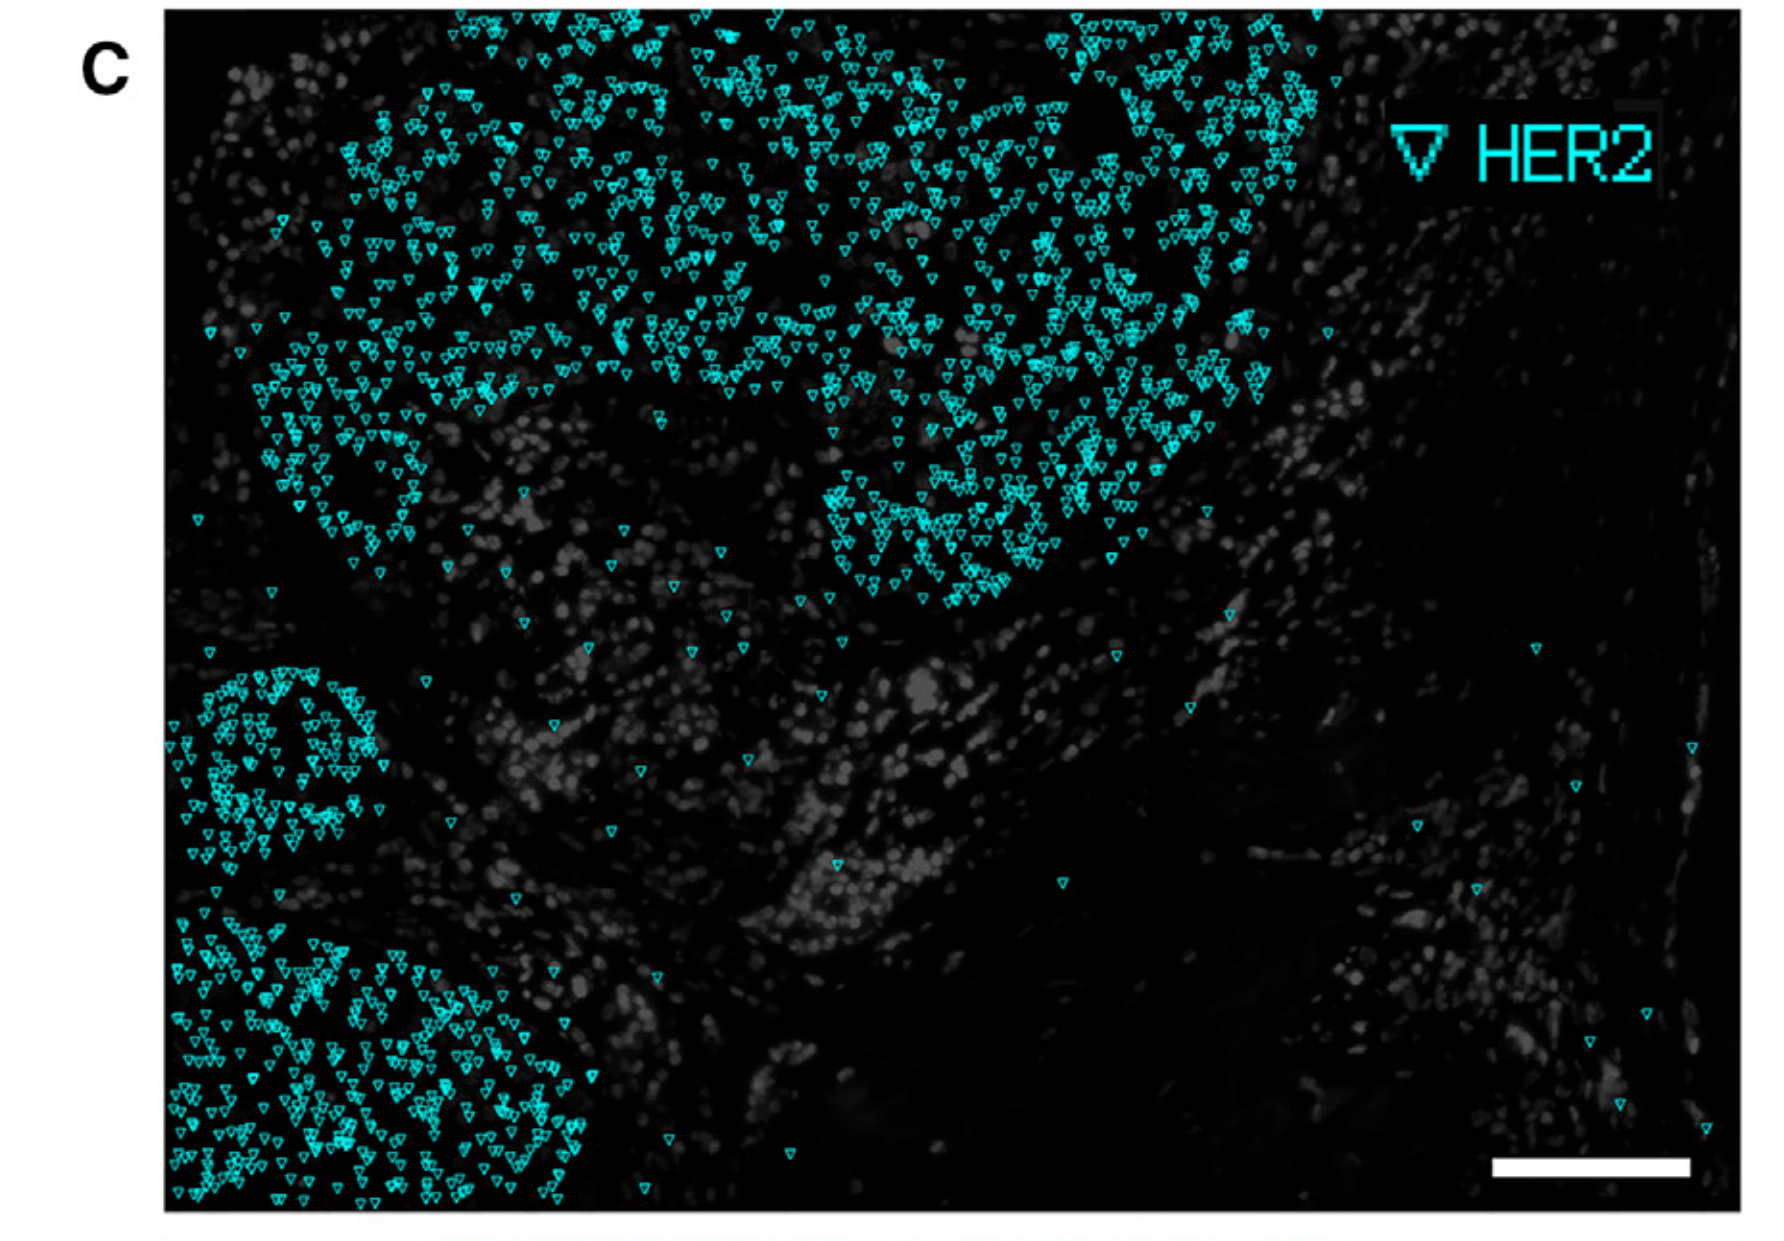

Yan Y. and Luo X. - 2025

BACT: nonparametric Bayesian cell typing for single-cell spatial transcriptomics data

Condition Dimension

N/A

Data Components

Biological AnnotationGene Expression Matrix

Data

Modality

Imaging-based

Resolution of observation

Sub-cellular

Visualized Elements

Observation

Biological

Tissue

Abstraction

None

Chart Type

Flourescence tissue imageScatterplot

Communicative/Contextualization

None

Comparative Design

Juxtaposition : Small multiples

Layout

Spatial : Physical

Scalability Strategy

None (Item-level)